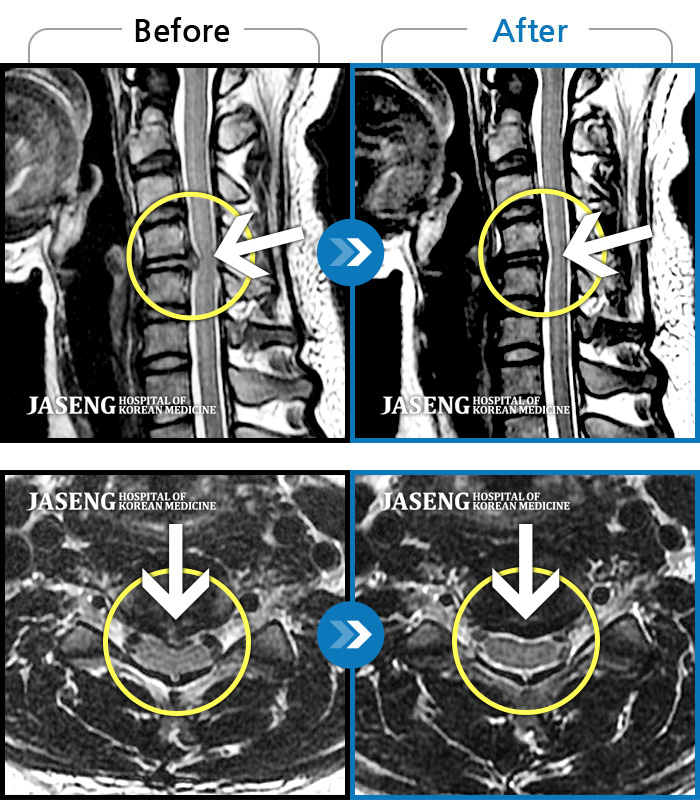

[뱸] 19.11.28~25.05.06